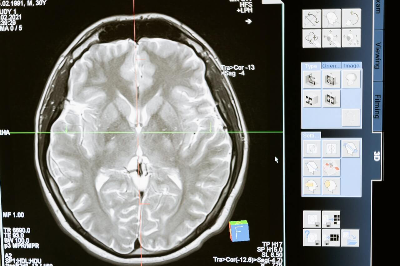

전문 영상 검사인 뇌혈관 조영술은 모야모야병 진단의 표준입니다.

MRI 및 CT 스캔과 같은 다른 영상 검사도 혈류 및 뇌 구조를 평가하는 데 도움이 될 수 있습니다.